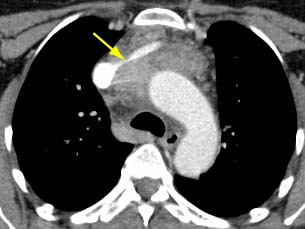

Quando o contraste intravenoso iodado é contraindicado, a ressonância nuclear magnética (RNM) do tórax pode ser usada para o estadiamento. Em geral, é menos útil que a TC porque os detalhes do tumor não estão definidos tão claramente. No entanto, a RNM com deslocamento químico pode ser útil na diferenciação entre hiperplasia tímica e tumor tímico.[26] Além disso, a RNM com sincronização cardíaca pode ser útil se houver suspeita de invasão cardíaca. A RNM também pode ser útil na diferenciação entre um tumor sólido e um cisto tímico benigno.[27] A PET-CT com fluordesoxiglucose (FDG) 18F pode ser usada para ajudar a diferenciar entre timoma (menos ávido por FDG) e linfoma (mais ávido por FDG) para tumores não invasivos distintos.[22] No entanto, se o tumor parece agressivo no exame de imagem, o resultado da PET não elimina a necessidade de uma biópsia percutânea com agulha grossa para diferenciar a neoplasia maligna tímica do linfoma, e para estabelecer um diagnóstico para terapia neoadjuvante ou terapia não cirúrgica definitiva.[28][29] A PET-CT também pode ser útil na demonstração de doença nodal ou metastática não suspeita; isso é útil quando os resultados de imagem ou histológicos sugerem um tumor agressivo.[30] De forma geral, à medida que a histologia da OMS se agrava, a intensidade de captação da PET (valor padronizado de captação) aumenta.[Figure caption and citation for the preceding image starts]: Tomografia computadorizada (TC) do tórax mostrando um típico timoma em estádio I de Masaoka-KogaDo acervo de Cameron Wright, MD; usado com permissão [Citation ends].

[Figure caption and citation for the preceding image starts]: Tomografia computadorizada (TC) do tórax mostrando timoma com encarceramento e invasão da veia inominada esquerdaDo acervo de Cameron Wright, MD; usado com permissão [Citation ends].